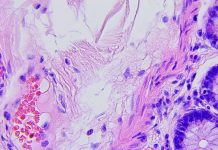

Glioblastoma multiforme (GBM) is an aggressive and life-threatening form of brain cancer. Although brain cancers as a whole are relatively uncommon, GBM are the most common type of malignant brain tumour in adults. The most common symptoms that appear are relatively innocuous – recurring headaches, difficulty thinking and speaking, blurry vision and unusual changes in mood or personality – making early detection a challenge. Patients often display advanced disease at the time of diagnosis reducing the therapeutic window of opportunity.

If cancer is considered the emperor of all maladies, then it is fair to say that cancer stem cells (CSCs) are the seeds that spread this evil. Cells within highly aggressive tumours, such as GBM, display poorly differentiated characteristics including high expression of genes enriched in pluripotent embryonic stem cells (ESCs) posing molecular parallels between the stem cell pheno- type, induced pluripotency, and cancer. In GBM, transcriptome analysis of clinical samples identified distinct subtypes based on molecular signatures (i.e. mesenchymal, classical, and proneural) with the mesenchymal subtype, thought to be the most aggressive, sharing a high-degree of similarity with stem cells at the transcriptome and epigenetic level2.

Moreover, single-cell analysis shows GBM cells exist in at least four different cellular states and can transition dynamically between molecular subtypes depending on cell-intrinsic and extrinsic factors3. This high-degree of transcriptional and epigenetic adaptability is thought to influence the emergence of therapy-resistant GBM cell sub-populations and plays a pivotal role in establishing intra-tumour heterogeneity4.